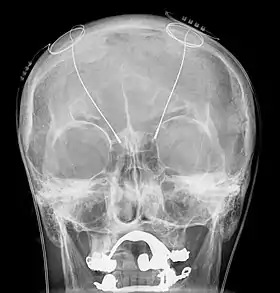

Components and placement

The DBS system consists of three components: the implanted pulse generator (IPG), the lead, and an extension. The IPG is a battery-powered neurostimulator encased in a titanium housing, which sends electrical pulses to the brain that interfere with neural activity at the target site. The lead is a coiled wire insulated in polyurethane with four platinum-iridium electrodes and is placed in one or two different nuclei of the brain. The lead is connected to the IPG by an extension, an insulated wire that runs below the skin, from the head, down the side of the neck, behind the ear, to the IPG, which is placed subcutaneously below the clavicle, or in some cases, the abdomen.[8] The IPG can be calibrated by a neurologist, nurse, or trained technician to optimize symptom suppression and control side effects.[35]

DBS leads are placed in the brain according to the type of symptoms to be addressed. For non-Parkinsonian essential tremor, the lead is placed in either the ventrointermediate nucleus of the thalamus or the zona incerta;[36] for dystonia and symptoms associated with PD (rigidity, bradykinesia/akinesia, and tremor), the lead may be placed in either the globus pallidus internus or the subthalamic nucleus; for OCD and depression to the nucleus accumbens; for incessant pain to the posterior thalamic region or periaqueductal gray; and for epilepsy treatment to the anterior thalamic nucleus.

All three components are surgically implanted inside the body. Lead implantation may take place under local anesthesia or under general anesthesia ("asleep DBS"), such as for dystonia. A hole about 14 mm in diameter is drilled in the skull and the probe electrode is inserted stereotactically, using either frame-based or frameless stereotaxis.[37] During the awake procedure with local anesthesia, feedback from the person is used to determine the optimal placement of the permanent electrode. During the asleep procedure, intraoperative MRI guidance is used for direct visualization of brain tissue and device.[38] The installation of the IPG and extension leads occurs under general anesthesia.[39] The right side of the brain is stimulated to address symptoms on the left side of the body and vice versa.